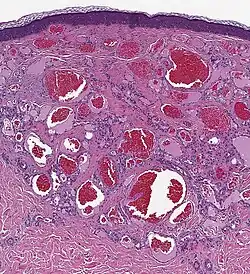

Histologie

- lobuläres Gefäßmuster des vaskulären, kanalisierten Tumors

- fokale Mikrothromben

- mittelkalibrige, arborisierende Gefäße

- Histologie eines Hämangioms